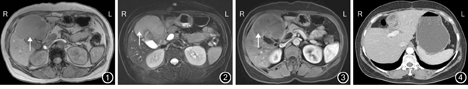

患者女,53岁。因右季肋区隐痛不适2个月余,于2014年6月15日入住我院。体格检查:患者皮肤、巩膜无黄染,全腹无压痛及反跳痛,右侧肋缘下扪及质地坚硬包块。实验室检查:ALT 30 U/L,Alb 36.5 g/L,TBil 10 μmol/L,AFP 2.1 μg/L、CEA 49.4 μg/L,CA19-9 20 U/L,HBsAg阴性。肝脏MRI检查示:胆囊底及胆囊窝邻近肝实质内见不规则长T1、长T2信号软组织包块,边界清晰,胆囊底壁显示不清晰,胆囊壁略增厚;弥散加权成像示弥散明显受限;肝实质内包块呈轻度渐进性强化;肝内包块邻近肝内脉管受累及。腹膜后、门腔静脉间隙见增大淋巴结。见图1,图2,图3。术前诊断:胆囊癌肝转移待查。

2014年6月20日,患者在气管插管麻醉下行肝脏肿瘤切除+胆囊切除+腹腔淋巴结清扫术。术中情况:无腹腔积液,胃肠、胰腺、脾脏及盆腔器官无异常。肿瘤位于肝右叶Ⅴ、Ⅵ段,质地坚硬,膨胀生长,边界清楚,大小为8 cm×9 cm,侵犯胆囊底部,压迫右胆管,肝十二指肠韧带和胰头后见肿大淋巴结,质地坚硬,考虑肿瘤转移。故术者决定行肝脏肿瘤切除+胆囊切除+腹腔淋巴结清扫术。术者首先解剖肝十二指肠韧带,清扫肝十二指肠韧带和胰头后方肿大淋巴结,解剖Calot三角,分别分离并结扎胆囊动脉及胆囊管,整块切除胆囊。距离肿瘤2 cm划定切缘,分离并完整保留右肝管,完整切除肿瘤。术后病理学检查示:肝脏原发性神经内分泌癌(primary hepatic neuroendocrine carcinoma,PHNEC),G3级,切除肿瘤标本总面积为10 cm×7 cm,脉管内查见癌栓;胆囊底受侵犯;胆囊管及肝脏切缘未见癌细胞,区域淋巴结转移(2/2)。免疫组织化学染色检测:细胞角质蛋白7、细胞角质蛋白19、CEA、突触素、黏附分子CD56表达均为阳性,抑癌基因P53、血清磷脂酰肌醇蛋白聚糖3、肝细胞石蜡抗原、嗜铬素A、神经元特异性烯醇酶表达均为阴性,增殖细胞核抗原Ki-67阳性率为20%~30%。患者术后于我院肿瘤科定期随访,并采用"依托泊苷+奈达铂"方案,行4个周期化疗。患者术后1年,未见肿瘤复发(图4)。

临床上根据其是否出现类癌综合征,分为功能性和非功能性两类。文献报道少数PHNEC患者具有类癌综合征,该临床症状有助于本病的术前诊断[2]。PHNEC影像学检查结果多表现为边界清晰的富血供包块,随着肿瘤的生长,肿瘤中央可见坏死液化区。PHNEC少见脉管癌栓,多无血管、淋巴管侵犯及腹腔淋巴结转移。PHNEC的MRI检查结果示:T1WI低信号,T2WI高信号,弥散加权成像弥散受限,增强扫描呈渐进性强化,延迟扫描为相对低信号,本研究结果与其相似[1,3]。PHNEC的诊断需具备以下条件:(1)排除肝外原发病灶。(2)嗜铬素A、突触素、神经元特异性烯醇化酶等神经内分泌标志物免疫组织化学染色检测呈阳性表现[4]。本例患者符合上述诊断标准。